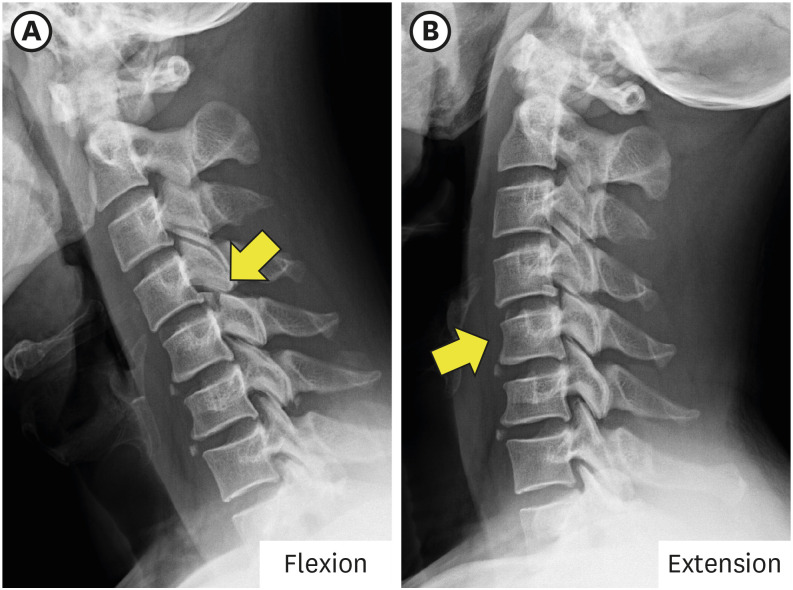

一名 42 岁男子从树上摔下后出现颈部疼痛。脊柱计算机断层扫描(CT)显示右侧 C5 上关节突骨折,无移位。磁共振成像(MRI)证实了骨折和后韧带复合体损伤。起初,由于没有不稳定或椎体错位的迹象,他接受了颈部支撑的保守治疗。然而,出院三天后,右肩无力和右上臂麻木的症状开始突出。X光片和CT显示,C4椎体前滑,C4/5椎面锁定,C5上关节突骨折骨片被锁定的C4下关节突推向前方,侵入神经孔。采用同种异体移植和钢板/螺钉固定,进行了颈椎前路椎间盘切除和融合术(ACDF)。虽然最初的影像学检查未显示有脱位迹象,但外科医生应注意隐匿性不稳定性以及与单侧颈椎面骨折相关的延迟脱位的可能性。

A 42-year-old man presented with neck pain after a fall from a tree. Spine computed tomography (CT) illustrated the right C5 superior articular process fracture without displacement. Magnetic resonance imaging (MRI) confirmed the fracture and injury of the posterior ligament complex. Initially he was managed conservatively with a neck brace as there were no signs of instability or vertebral body misalignment. However, three days after discharge, right shoulder weakness and numbness of the right upper arm became prominent. X-rays and CT showed anterior slippage of the C4 vertebral body and locked C4/5 facet ??a fractured bony fragment of the C5 superior articular process was pushed forward by the locked inferior articular process of C4 and invaded the neural foramen. Anterior cervical discectomy and fusion (ACDF) was performed using allograft and plate/screws fixation. Although initial imaging showed no evidence of subluxation, surgeons should be aware of occult instability and the possibility of delayed dislocation associated with the unilateral cervical facet fracture.